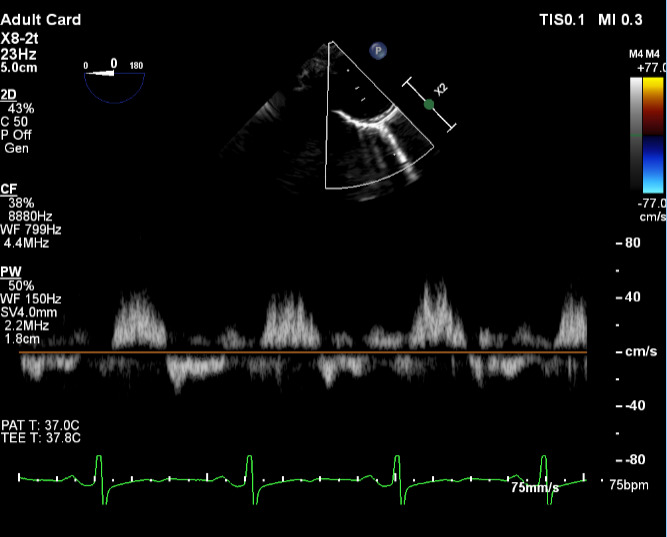

Brain and neck magnetic resonance angiography (MRA) showed no acute or significant vascular abnormality. Transesophageal echocardiogram showed severe aortic regurgitation, trileaflet thickened aortic valve, enlarged ascending aorta 45 mm, normal left ventricular systolic function and patent foramen ovale (Figure 1, Figure 2 and Figure 3). Calculated aorta size index (aortic size cm/body surface area m2) was moderate-severely increased, 2.7 cm2/m2. Mild immobile atherosclerosis of the aorta was noted.

Although transesophageal echocardiogram identified mild immobile thoracic aorta atherosclerosis and a patent foramen ovale (PFO), two potential sources for embolic stroke, the definitive etiology of stroke was not clear. Extended two-week rhythm monitor showed no atrial fibrillation or atrial flutter. Hypercoagulable lab workup was negative. Lipoprotein(a) was elevated at 118 nmol/L.